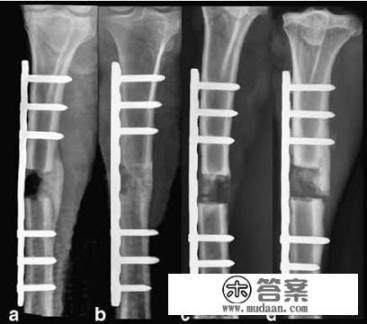

骨不连手术需要植骨

无论是否经过手术,骨折以后都有可能出现骨不连,这种情况多见于患者的身体状态比较差,骨折的折端之间有软组织嵌插阻碍的了血供或者是骨折手术折端之间距离过远等很多因素都可以导致骨不连。

一般情况下,骨折石膏固定或者切开手术术后6~9个月没有骨痂生长既可以判定为骨不连,此时在以往的处置过程当中,一般要给予骨折部位切开,将骨折两端新鲜化,打通闭塞的血管,或者是去除掉阻碍骨折生长的结构比如瘢痕,然而单纯的做这些图纸并不能促进骨折的愈合,在成就骨头的两端,我们需要新鲜的骨质进行补充,而且这些骨质不仅要有骨框架的作用还应该要有骨诱导作用,所以取自体骨植骨是一种比较好的选择。